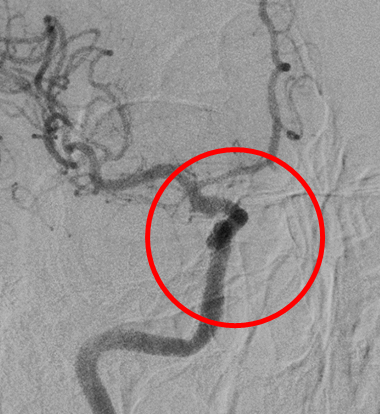

破裂内頚動脈瘤

術後の造影写真です。主幹動脈は温存できており、動脈瘤は造影されなくなっています。

術後4週間、動脈瘤の再発はありません。

術後6か月、動脈瘤は完全に消失しています。